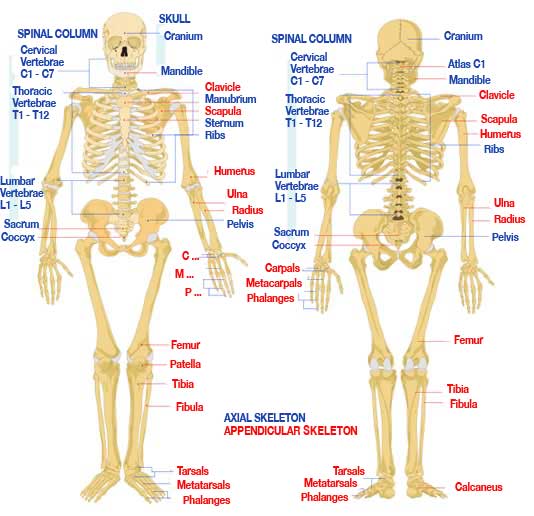

- Main bones of the skeletal system e.g. skull, humerus

MAIN BONES OF THE SKELETAL SYSTEM

The main bones of the skeletal system are:

1. Cranium (skull)

2. Orbit (eye)

3. Jaw bone

4. Cervical vertebra (neck bone)

5. Vertebral column

6. Scapula (shoulder blade)

7. Clavicle (collar bone)

8. Sternum (breast bone)

9. Ribs

10. Thoracic vertebra

11. Humerus (upper arm bone)

12. Radius and ulna (lower arm bone)

13. Carpals (wrist bone)

14. Phalanges (finger bones)

15. Femur (thigh bone)

16. Tibia and fibula (leg bones)

17. Patella (knee bone)

18. Tarsals (ankle bone)

19. Phalanges (toe bones)

MAIN BONES OF THE SKELETAL SYSTEM

The main bones of the skeletal system are:

1. Cranium (skull)

2. Orbit (eye)

3. Jaw bone

4. Cervical vertebra (neck bone)

5. Vertebral column

6. Scapula (shoulder blade)

7. Clavicle (collar bone)

8. Sternum (breast bone)

9. Ribs

10. Thoracic vertebra

11. Humerus (upper arm bone)

12. Radius and ulna (lower arm bone)

13. Carpals (wrist bone)

14. Phalanges (finger bones)

15. Femur (thigh bone)

16. Tibia and fibula (leg bones)

17. Patella (knee bone)

18. Tarsals (ankle bone)

19. Phalanges (toe bones)